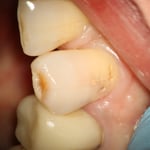

上顎の第二小臼歯遠心隣接面の虫歯。症状が出る前に治療をすれば、治療する側もされる側も楽になります。

下顎左側第二小臼歯。大きな虫歯でしたが、神経を除去せずにこんなに綺麗に復活できました。見た目で判断することは厳禁です。やってみないとわからない事は多くあります。術後の歯髄診でも生活反応はもちろんあります。